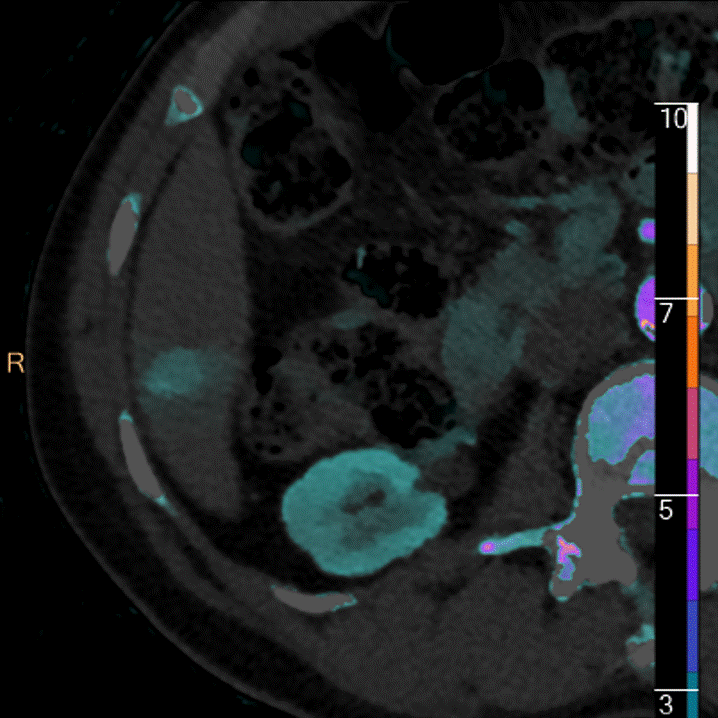

Something new for adrenal nodules